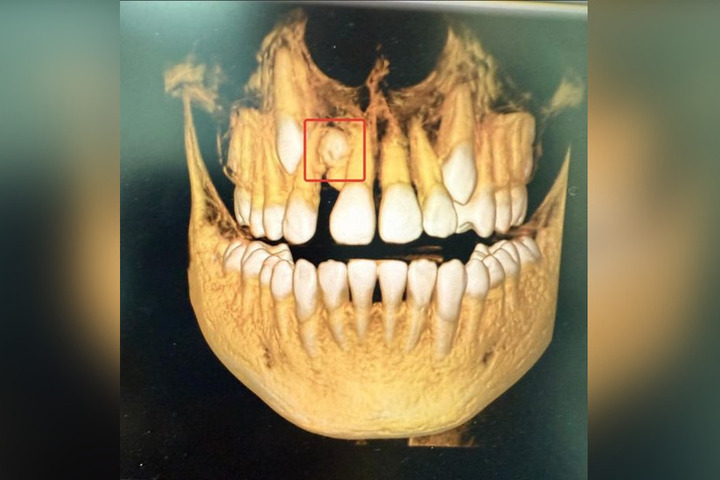

В столице Башкирии врачи стоматологической поликлинике №17 удалили сверхкомплектный зуб 13-летнему школьнику.

Как сообщили в минздраве республики сообщили, что такая аномалия встречается в одном из 1000 случаев. Ребенок обратился к ортодонту с жалобами на эстетические проблемы. На КТ врачи обнаружили лишний зуб в верней челюсти, между центральным и боковым резцом.